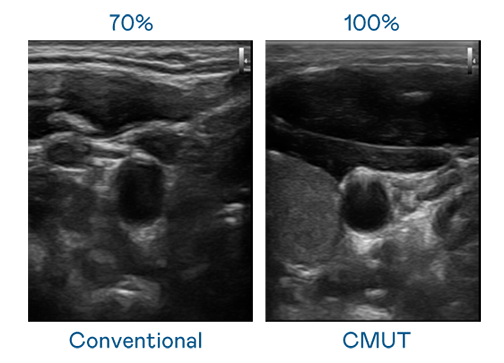

CMUT 技术是一种用电容式微机电元件来产生超音波讯号的技术。与传统 PZT 压电式技术相比,CMUT 频宽增加 30%,更宽频的超音波讯号让影像解析度大幅提升,是实现高影像品质医疗超音波扫描、促进精准医疗发展的关键技术。

大频宽带来超清晰影像

超音波影像的解析度高低,首先取决于探头能发出的讯号频宽。币游国际 CMUT 可提供高清晰的超音波讯号,提供高频宽、高灵敏度、影像纹理细节更高的超音波影像,协助医护人员缩短影像判读时间及利用精准的医疗影像进行诊断。